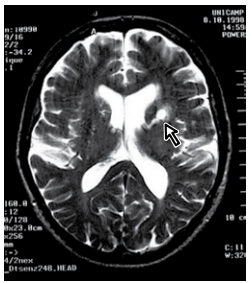

Um paciente de 75 anos com histórico de hipertensão e

fibrilação atrial em uso de rivaroxabana (20 mg/dia) apresenta disartria súbita. A ecocardiografia transtorácica revelou dilatação moderada do átrio esquerdo e hipertrofia

ventricular esquerda, mas sem trombos intracardíacos.

O monitoramento contínuo não detectou fibrilação atrial

adicional. A avaliação inicial com ressonância magnética

encontra-se a seguir.